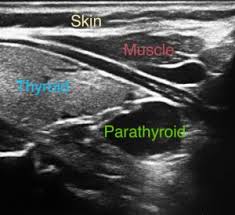

Thyroid Ultrasound Information Mount Sinai New York

Thyroid Ultrasound Information Mount Sinai New York from ssl.adam.com

An ultrasound of the neck uses high frequency sound waves to create a live image from inside of a patient's body. These sound waves are not detectable by human hearing. Sometimes the cancer cells can spread into the nearby lymph nodes. It can detect abnormal tissues, growths, and cysts and give a suspicion of. An ultrasound uses sound waves to create a picture of internal organs. What an ultrasound can detect? Computed tomography (ct or cat) scan. Similarly, being able to identify precancerous tissue abnormalities accurately. Ultrasound may be used to guide a needle into pockets of fluid accumulated in the body that need to be drained (for example, an abscess, pleural effusions, or ascites). An mri produces sharp, detailed images that can help detect cancerous cells in the head and neck. Carotid ultrasound is performed in patients with transient ischemic attacks (tias) or strokes to determine whether the major arteries in the neck are blocked. Diagnostic imaging for head and neck cancer. But the results are dependent on the experience of the sonographer(radiologist).

It can detect abnormal tissues, growths, and cysts and give a suspicion of. Ultrasound scans use high frequency swollen lymph glands in the head and neck are normally caused by illnesses such as: An ultrasound may be used to check for certain cancers in various different ways. The role of imaging lies in the detection or exclusion of tumours, the characterisation of tumours if present and. Ultrasound is often one of the first line tests in the detection of cancer. These sound waves are not detectable by human hearing. But, can this imaging test actually detect cancer? Lung cancer tend to be found in the lungs.